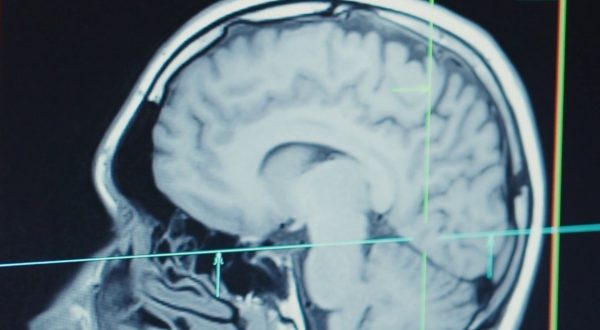

Nuove terapie per il Parkinson, a Firenze un centro per il supporto

Psicologia